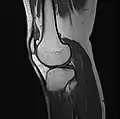

Imaging

MRI

Both anterior cruciate ligament (ACL) and posterior cruciate ligaments (PCL) are hypointense on both T1 and T2 weighted images of MRI. However, some high signal striations are often seen at the distal part of the ACL, making ACL higher intensity than PCL on MRI scans.[17]